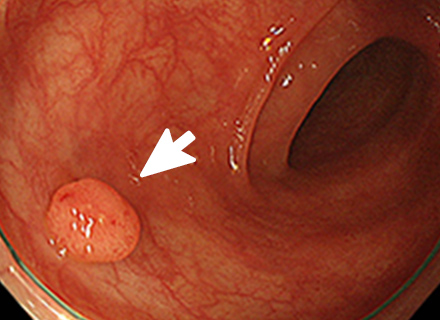

大腸ポリープまたは早期大腸がんの内視鏡治療

良性のポリープや早期がんの中でも粘膜だけにとどまっているもの、粘膜下層へわずかに広がっているものが内視鏡治療の適応となります。 小さなポリープに対しては、鉗子でつかみながら高周波電流を用いて病変の根もとを焼き切ります(ホットバイオプシー)。 茎のあるポリープに対しては、輪の形のスネアを茎の部分でしめ、高周波電流を用いて切断します(ポリペクトミー)。 茎のない病変に対しては、内視鏡的粘膜切除術(EMR)や内視鏡的粘膜下層剥離術(ESD)などを行います。